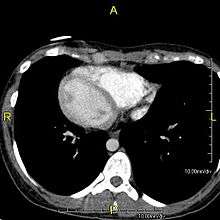

Situs inversus (also called situs transversus or oppositus) is a congenital condition in which the major visceral organs are reversed or mirrored from their normal positions. The normal arrangement of internal organs is known as situs solitus while situs inversus is generally the mirror image of situs solitus. Although cardiac problems are more common than in the general population, most people with situs inversus have no medical symptoms or complications resulting from the condition, and until the advent of modern medicine it was usually undiagnosed.

Situs inversus is found in about 0.01% of the population, or about 1 person in 10,000. In the most common situation, situs inversus totalis, it involves complete transposition (right to left reversal) of all of the abdominal organs. The heart is not in its usual position in the left chest, but is on the right, a condition known as dextrocardia (literally, right-hearted). Because the relationship between the organs is not changed, most people with situs inversus have no medical symptoms or complications, although they should wear a medical identification tag to warn emergency medical staff that the patient's internal organs are reversed from normal so they can act accordingly, e.g. by listening for a heartbeat on the right rather than left side of the chest.[1]

The condition affects all major structures within the thorax and abdomen. Generally, the organs are simply transposed through the sagittal plane. The heart is located on the right side of the thorax, the stomach and spleen on the right side of the abdomen and the liver and gall bladder on the left side. The heart's normal right atrium occurs on the left, and the left atrium is on the right. The lung anatomy is reversed and the left lung has 3 lobes while the right lung has 2 lobes. The intestines and other internal structures are also reversed from the normal, and the blood vessels, nerves, and lymphatics are also transposed.

If the heart is swapped to the right side of the thorax, it is known as "situs inversus with dextrocardia" or "situs inversus totalis". If the heart remains on the normal left side of the thorax, a much more rare condition (1 in 2,000,000 of the general population), it is known as "situs inversus with levocardia" or "situs inversus incompletus".